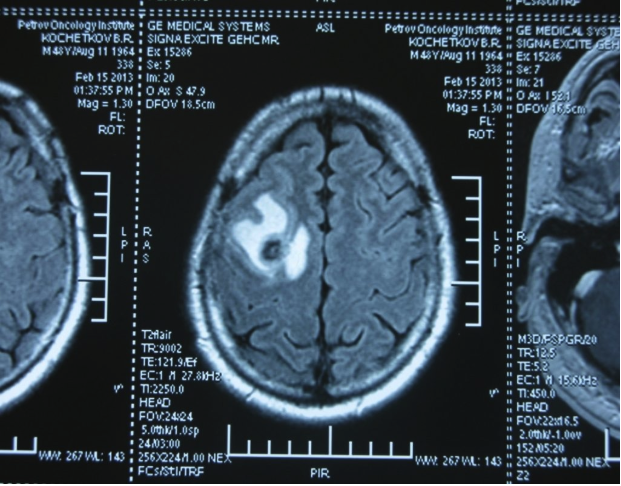

Головной мозг

Герминогенные новообразования в данной области – это примерно 2-4% от всех внутричерепных (интракраниальных). Патология в 75% случаев диагностируется у мальчиков, за исключением турецкого седла, где новообразования в основном локализуются у девочек.

Герминомы формируют инфильтрирующие опухоли больших размеров, часто являющиеся источниками субарахноидальных (между мягкой и паутинной оболочками мозга) и вентрикулярных (желудочковых) метастаз.

Risunok7.pngРисунок 7. – Герминома головного мозга.